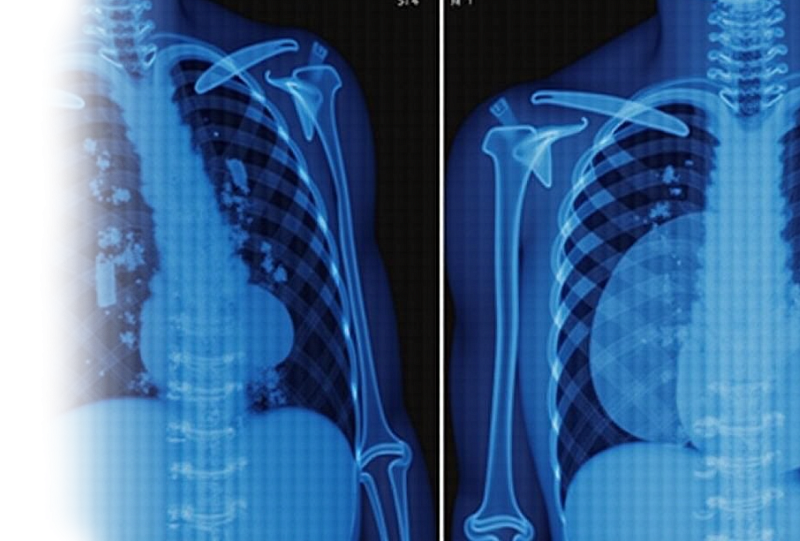

Компьютерная томография органов грудной клетки с виртуальной бронхоскопией – важный метод исследования состояния паренхимы легких, органов средостения, костного каркаса грудной клетки и мягких тканей с последующей визуалиацией просветов трахеи и крупных бронхов.

Показания для проведения КТ органов грудной клетки с виртуальной бронхоскопией:

• патологии паренхимы легких, органов средостения;

• построение 3D-реконструкции воздушных путей (трахеи и крупных бронхов) для оценки стеноза просвета;

• костно-травматические изменения каркаса грудной клетки;

• оценка изменений в мягких тканях грудной стенки.